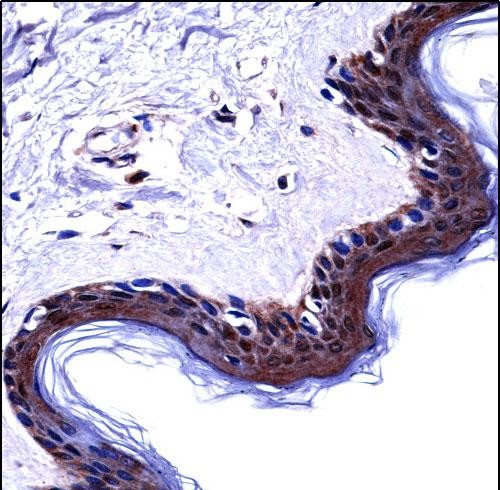

| IHC | 1/100-1/500 | Human,Mouse,Rat |

| Immunogen | This DSG1 antibody is generated from rabbits immunized with a KLH conjugated synthetic peptide between 471-499 amino acids from the Central region of human DSG1. |

Desmoglein 1 (DSG1) is a transmembrane glycoprotein belonging to the desmoglein subfamily of cadherins, primarily expressed in the stratified squamous epithelia of the skin and mucous membranes. It plays a critical role in maintaining epidermal integrity by forming desmosomes, specialized cell-cell junctions that provide mechanical strength. DSG1 antibodies are autoantibodies targeting this protein, commonly associated with autoimmune blistering disorders. The most notable condition linked to DSG1 antibodies is pemphigus foliaceus (PF), a superficial blistering disease where autoantibodies disrupt DSG1-mediated adhesion, leading to acantholysis (separation of epidermal cells) and blister formation.